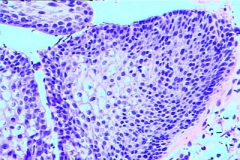

膀胱炎诱因有结石、异物、肿瘤或阻塞性病变,包括由于神经系统疾产生的排尿功能障碍等。膀胱炎的急性炎症的病理变化有粘膜充血、水肿、出血和溃疡形成,并有脓液或坏死组织。慢性炎症主要有粘膜增生或萎缩、肉芽组织形成,并有纤维组织增生,膀胱容量减少;或并发阻塞所引起的肌肉肥大,膀胱容量增大甚至有憩室形成等改变。还有一种特殊的炎症变化是坏疽性膀胱炎,为梭形杆菌、产气荚膜杆菌等引起的严重膀胱炎症。